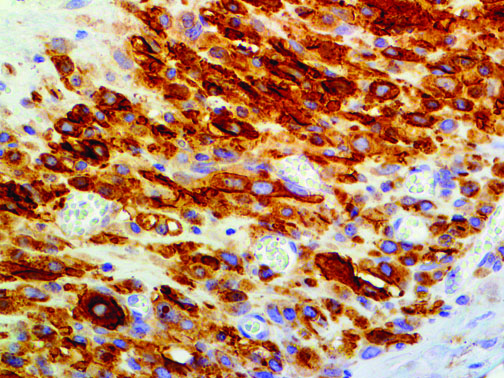

It is the ICU physician who is most likely to witness one of the deadliest manifestations of the abnormal immunological response, the cytokine storm syndrome (CSS). This response is also referred to by some as the cytokine release syndrome (CRS). CSS is characterized by continuous activation and expansion of macrophage and lymphocyte populations, which secrete large amounts of cytokines, causing the cytokine storm. This massive cytokine release is akin to hemophagocytic lymphohistiocytosis (HLH) disease, a syndrome characterized by initial unchecked and persistent activation of cytotoxic T lymphocytes and NK cells.

Clinical and laboratory manifestations of HLH include fever, enlarged liver and/or spleen, neurologic dysfunction, coagulopathy, liver dysfunction, cytopenias (i.e., low levels of erythrocytes, leukocytes, and/or platelets), hypertriglyceridemia, hyperferritinemia, hemophagocytosis, and eventually diminished NK cell activity as the immune system becomes progressively paralyzed. HLH can be familial (primary HLH) or secondary to another disease process (sHLH), such as rheumatic disease, in which it is referred to as macrophage activation syndrome (MAS, characterized by elevated ferritin).